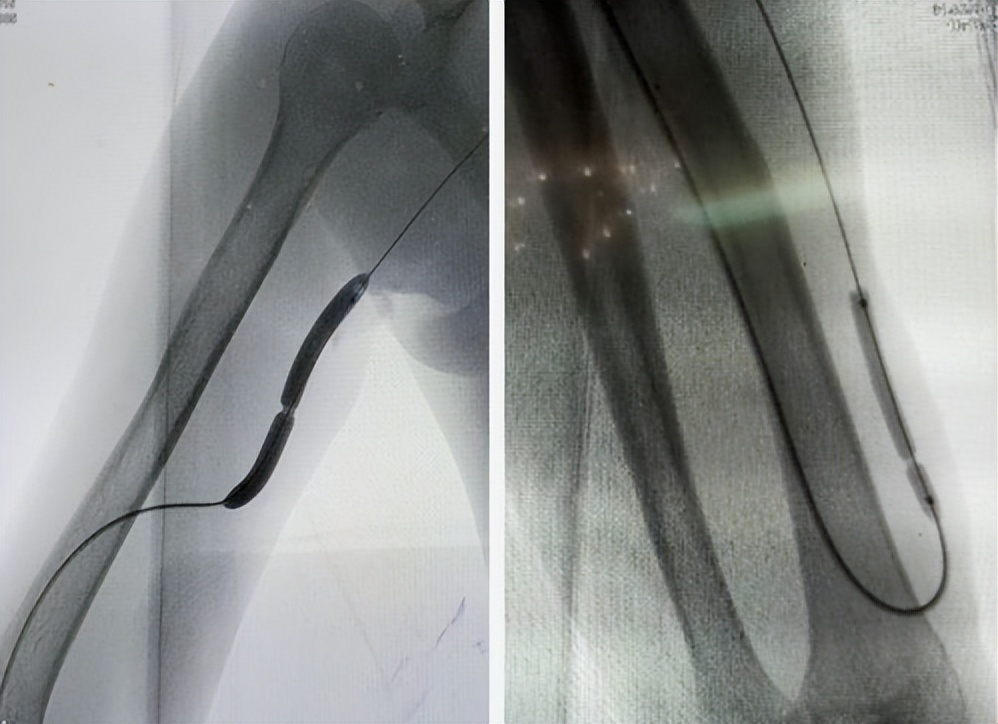

Score flex PTA 球囊扩张导管是一种带固有导丝和快速更换口的适用于外周动脉(包括膝下动脉)PTA的半顺应性PTA球囊导管。 产品主要有弹簧版和非弹簧版两种设计。

非弹簧版有一个工作长度为150cm的导管,其由导管座、带尼龙外套的海波管、固有导丝、远程管身、球囊及尖端组成。 被设计成与0.014英寸标准长度的导线兼容

弹簧版提供40cm、90cm及150cm的工作长度、并与0.014英寸或0.018英寸的导线兼容。